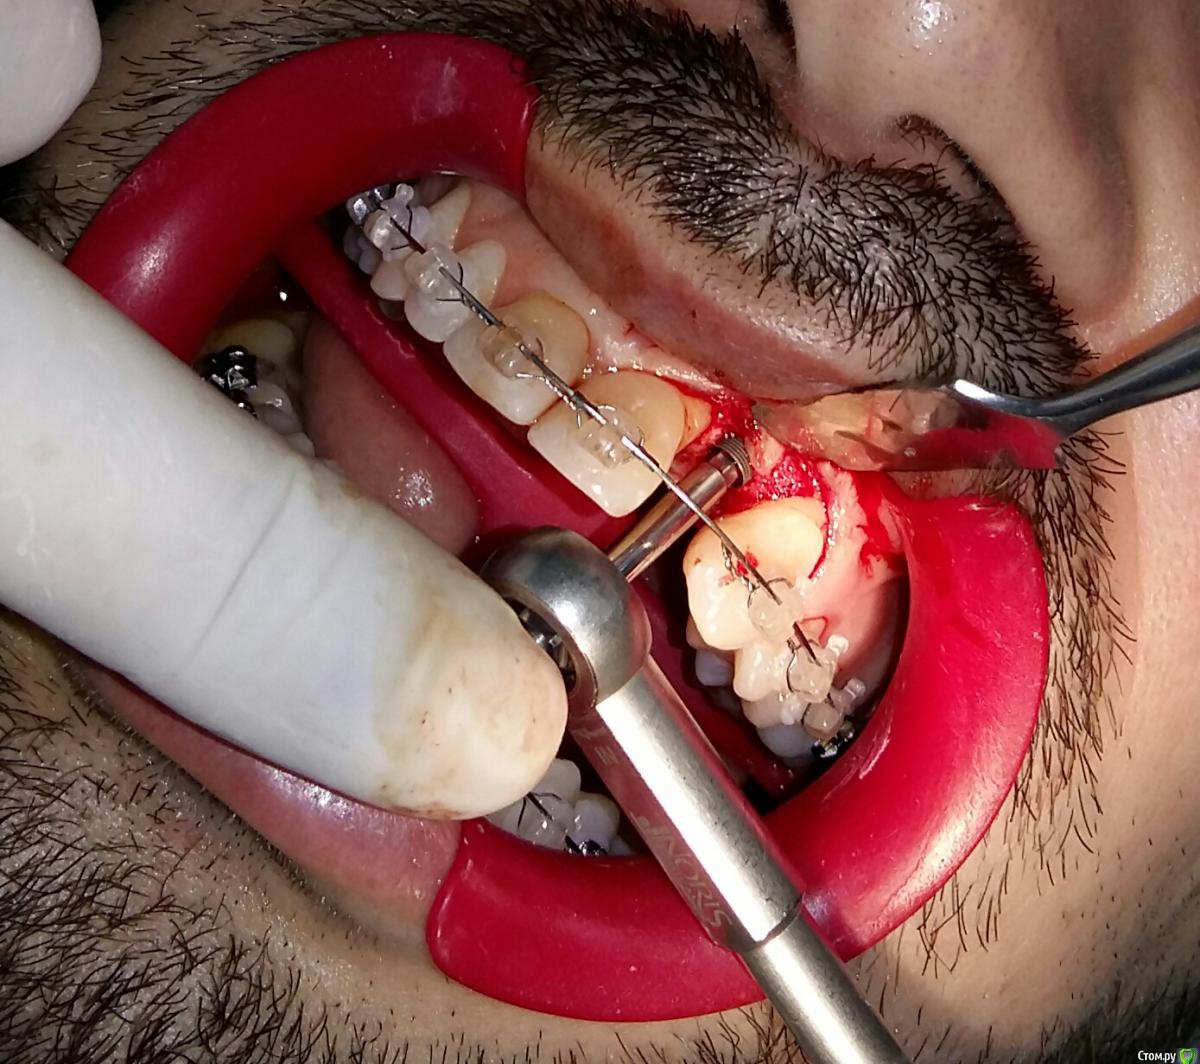

Kostoprav Опубликовано 8 июля, 2015 Поделиться Опубликовано 8 июля, 2015 ИЗНАЧАЛЬНАЯ СИТУАЦИЯ ПОЛУЧИЛОСЬ сори что нет фото до имплантации. Блок взял с тела челюсти, фиксировал двумя винтами (во время имплантации выкрутил только один), присыпал gen os, укрыл дермой-получил заметный прирост слизистой) имплант альфадент 3,75х11,5 2 Ссылка на комментарий

Kostoprav Опубликовано 8 июля, 2015 Автор Поделиться Опубликовано 8 июля, 2015 Видно что блок прирос. ЗдоровоОстальное оценить сложноМне нравится положение импланта в плане оси.Но уровень заглубления не ясенТакже не видно прироста десныВ общем мало данных для оценкиНо опять же вам именно она и нужна?по вестибюлярной поверхности заглубил приблизительно на 1мм с небной больше получилось. слизистая по сравнению с первым разом значительно толще стала, доказать к сожалению не могу так как не делал фото(: я выложил этот пост не только ради оценки, может кому из начинающих данный случай сгодиться 3 Ссылка на комментарий

Kostoprav Опубликовано 28 июля, 2015 Автор Поделиться Опубликовано 28 июля, 2015 Сколько времени прошло после фиксации блока? Чем забирает е блок? на момент имплантации 6 мес. забор блока делал линденманом Ссылка на комментарий